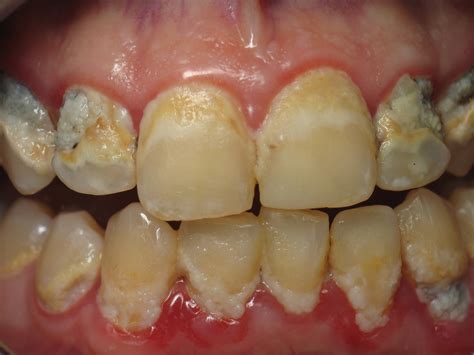

Periodontal disease is a silent, inflammatory condition that affects the tissues surrounding and supporting your teeth. It typically begins as gingivitis, characterized by inflammation, and can advance to periodontitis, which involves the destruction of bone and connective tissue. By examining Gum Disease Pictures, you can often identify the transition from healthy, firm, pink gums to tissues that appear puffy, red, or even receding.

• Gingivitis: The earliest stage where gums are inflamed, sensitive, and prone to bleeding while brushing.

• Early Periodontitis: The gums begin to pull away from the teeth, forming small pockets where bacteria can hide.

• Moderate to Advanced Periodontitis: Deep pockets form, bone support is lost, and teeth may become loose or shift, which is frequently documented in medical Gum Disease Pictures.

Common Visual Symptoms to Watch For

When you look at resources providing Gum Disease Pictures, you will notice consistent visual markers. Recognizing these early is essential to preventing permanent tooth loss. The following table highlights what you should look for compared to healthy tissue:

Visual Indicator Healthy Gums Signs of Disease

Color Firm, pale pink Deep red, purple, or bright red

Texture Stippled (orange peel texture) Smooth, shiny, or puffy

Margin Snug against the tooth Receding or showing gaps/pockets

Bleeding None Frequent bleeding during brushing